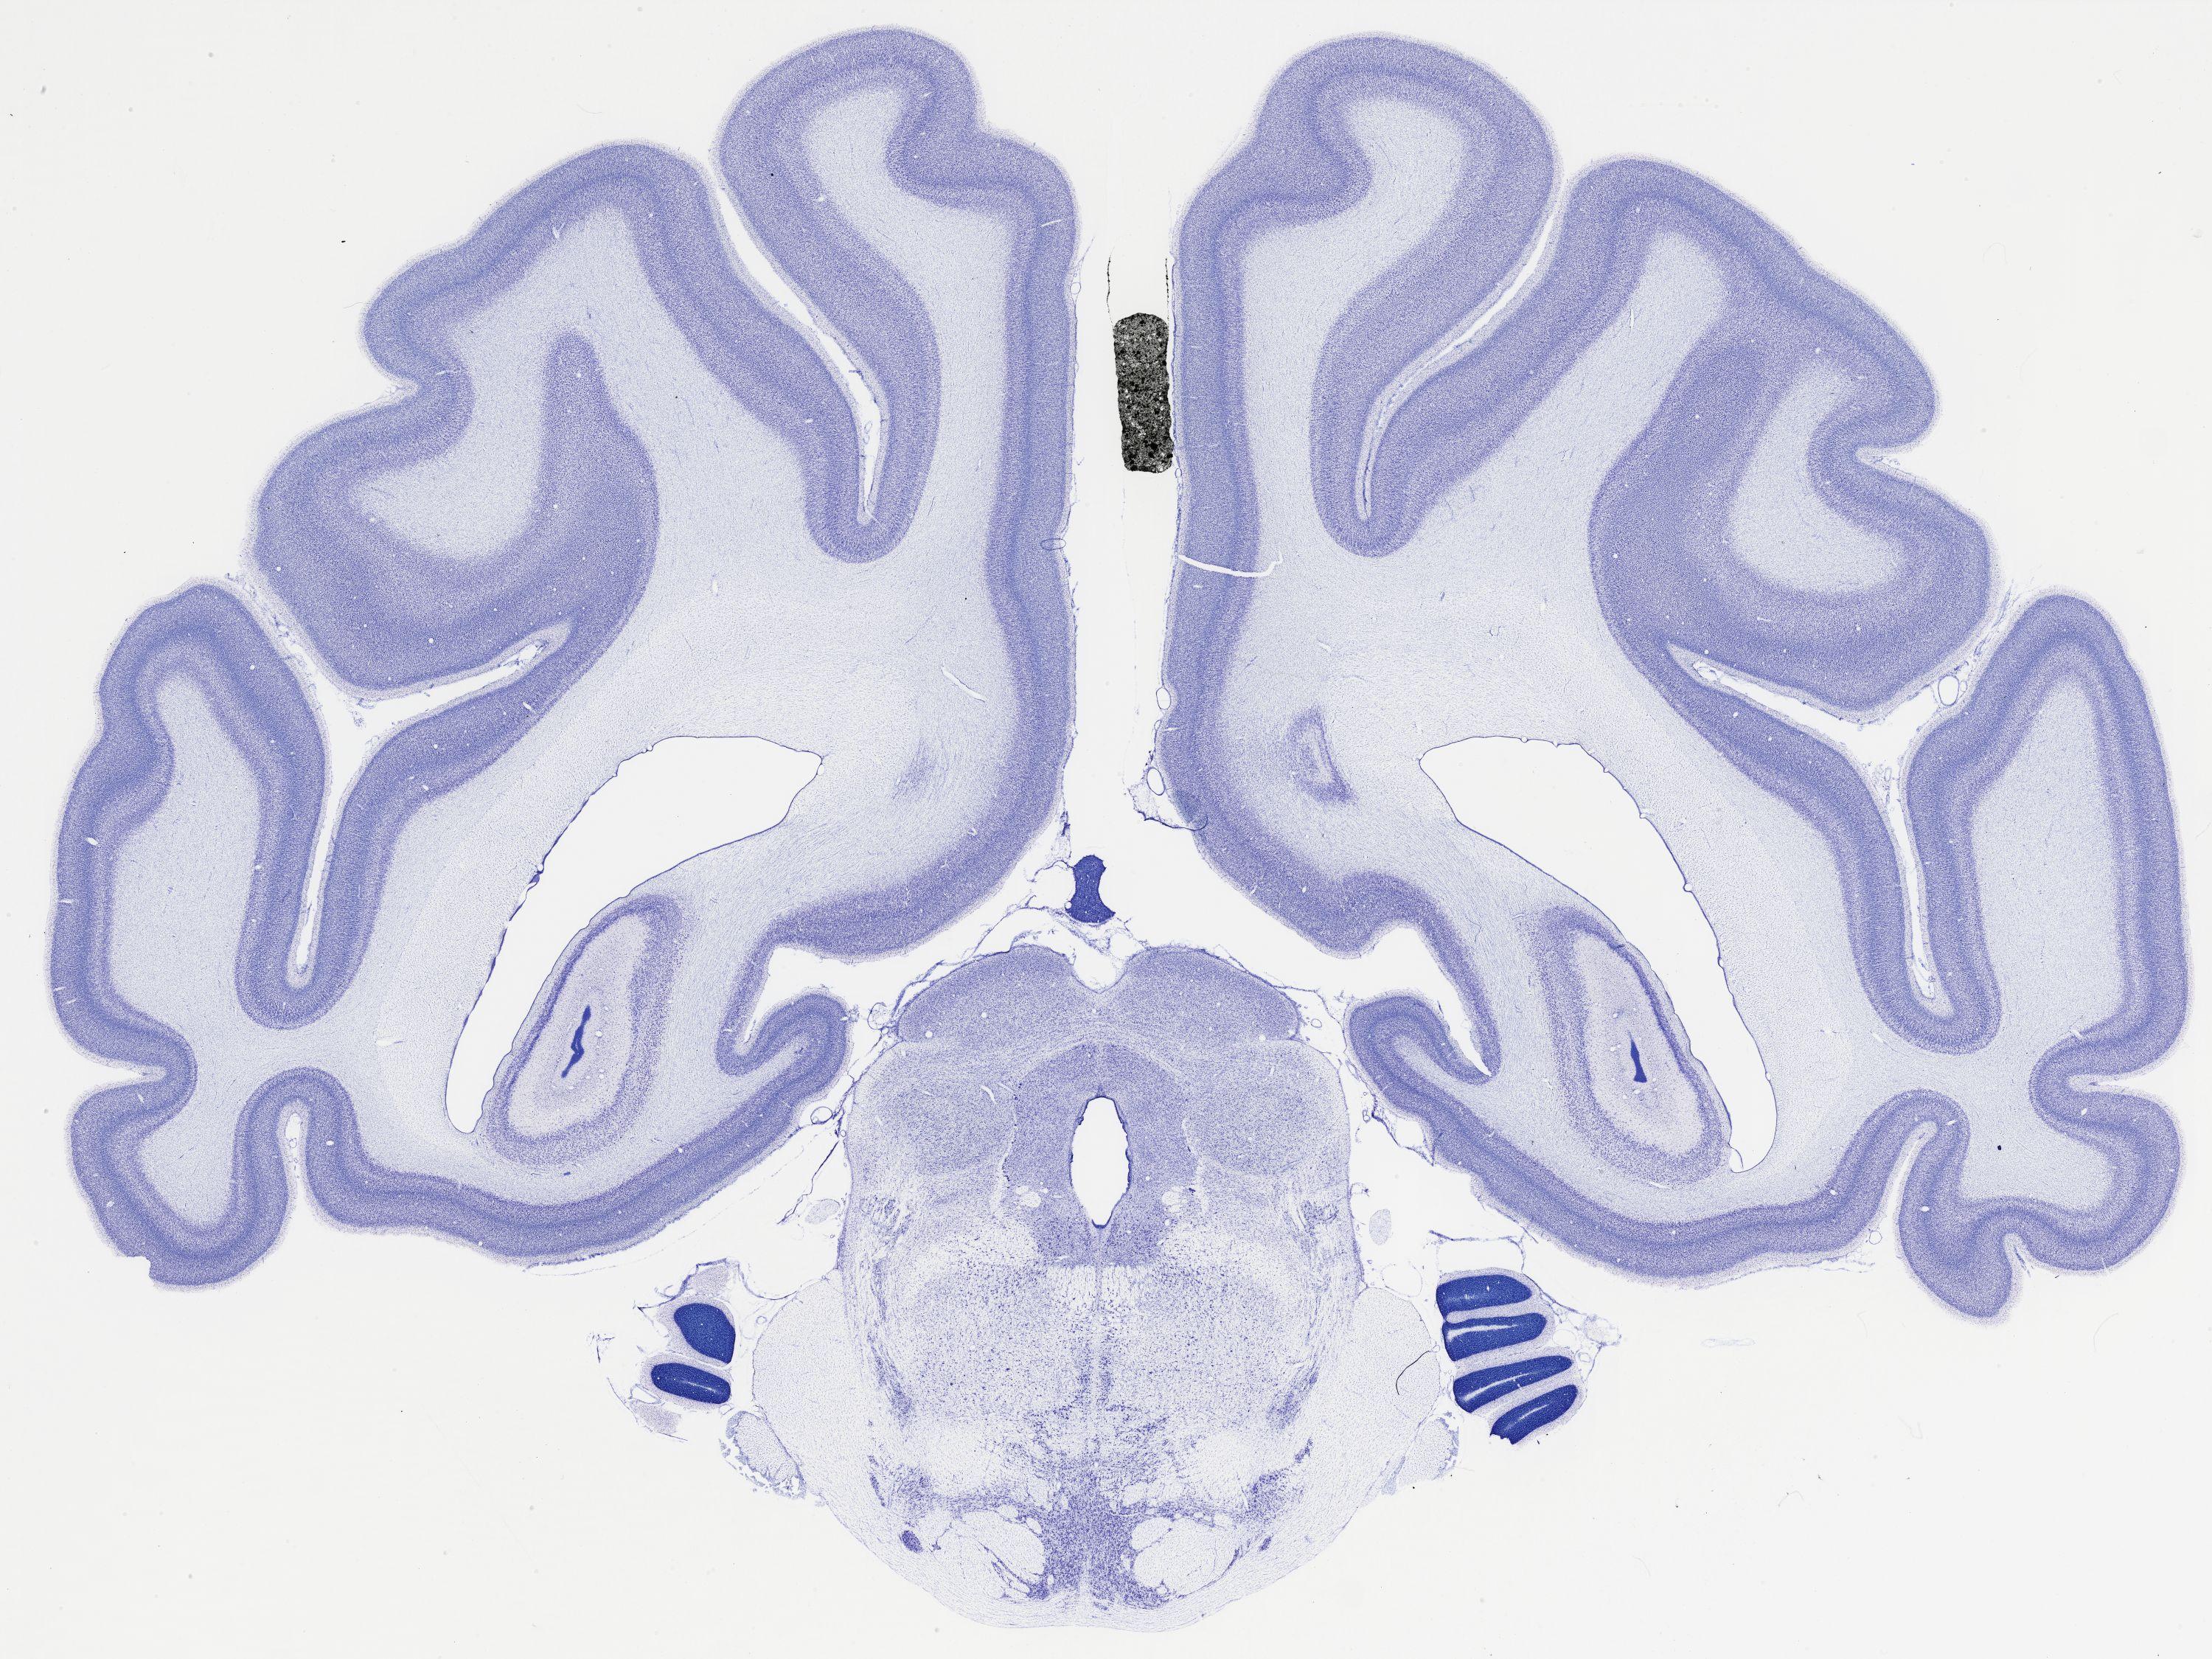

thumbnail

481